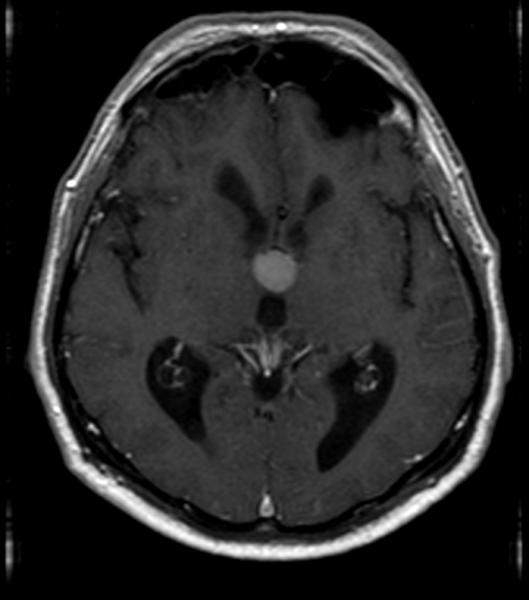

Ασθενής 63 ετών, προσέρχεται λόγω αναφερόμενων από το οικείο περιβάλλον διαταραχών βάδισης, πρόσφατης μνήμης και προσωπικότητας, συμτωματολογία αρχόμενη προ τριετίας.Υπεβλήθη σε μαγνητική τομογραφία εγκεφάλου η οποία ανέδειξε κυστική εξεργασία στο κατώτερο τμήμα της τρίτης κοιλίας (18x16x14mm), χαμηλού σήματος στις Τ2 ακολουθίες και υψηλού σήματος στις Τ1 (ως επί κολλοειδούς κύστης). Ο ασθενής αντιμετωπίστηκε αρχικά συντηρητικά, υπό παρακολούθηση με ετήσιο έλεγχο με μαγνητική τομογραφία. Από το περιβάλλον αναφέρεται προοδευτικά επιδείνούμενη συμτωματολογία κατά το τελευταίο εξάμηνο, για την οποία και αποφασίστηκε χειρουργική αντιμετώπιση.

Προεγχειρητικός απεικονιστικός έλεγχος